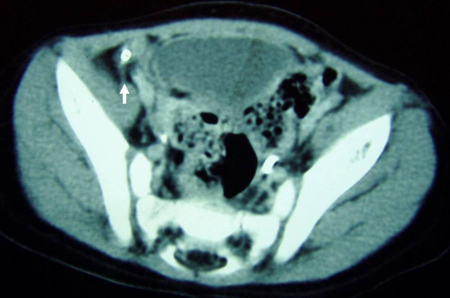

Tomografia computadorizada (TC) revelando fecalito (seta branca) fora do lúmen do apêndice consistente com apêndice perfurado

Do acervo de Dr. KuoJen Tsao; usado com permissão